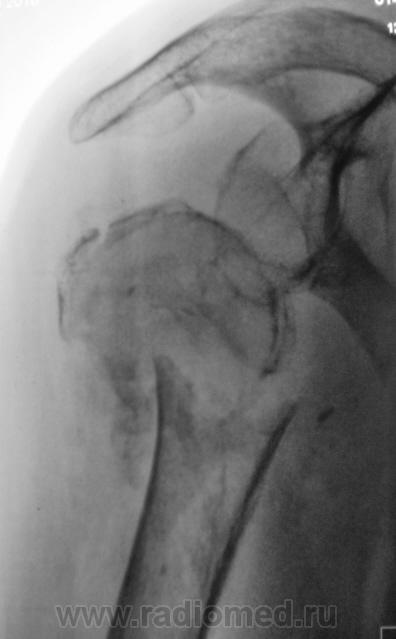

Травма. Пациентка "преклонного" возраста направлена на рентгенографию плечевого сустава.

головки плечевой кости. Вопрос только в том. будет ли этот прелом на фоне остеопороза или пат. изменённой костной ткани?

Вероятно перелом патологический, на фоне метастатического поражения. Показана рентгенография таза, черепа.

В лёгких (кусок лёгкого виден) синдром диссеминации с обеих сторон по типу карциноматоза.

очень похоже на метастаз рака почки.

Похоже, и на метастаз...